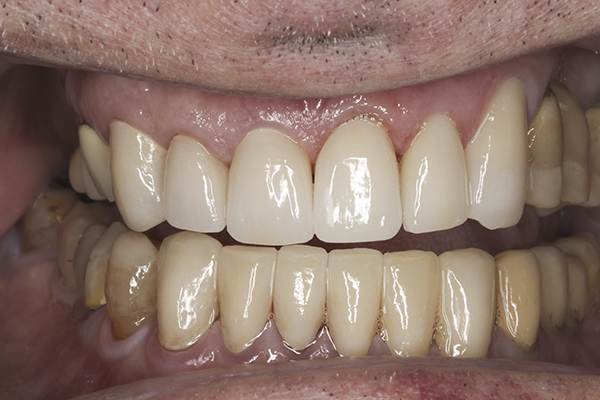

(35.) Postoperative right lateral, closed view.

Figure 35

(36.) Postoperative anterior, closed view. Note the position of the upper and lower canines to provide canine guidance.

Figure 36